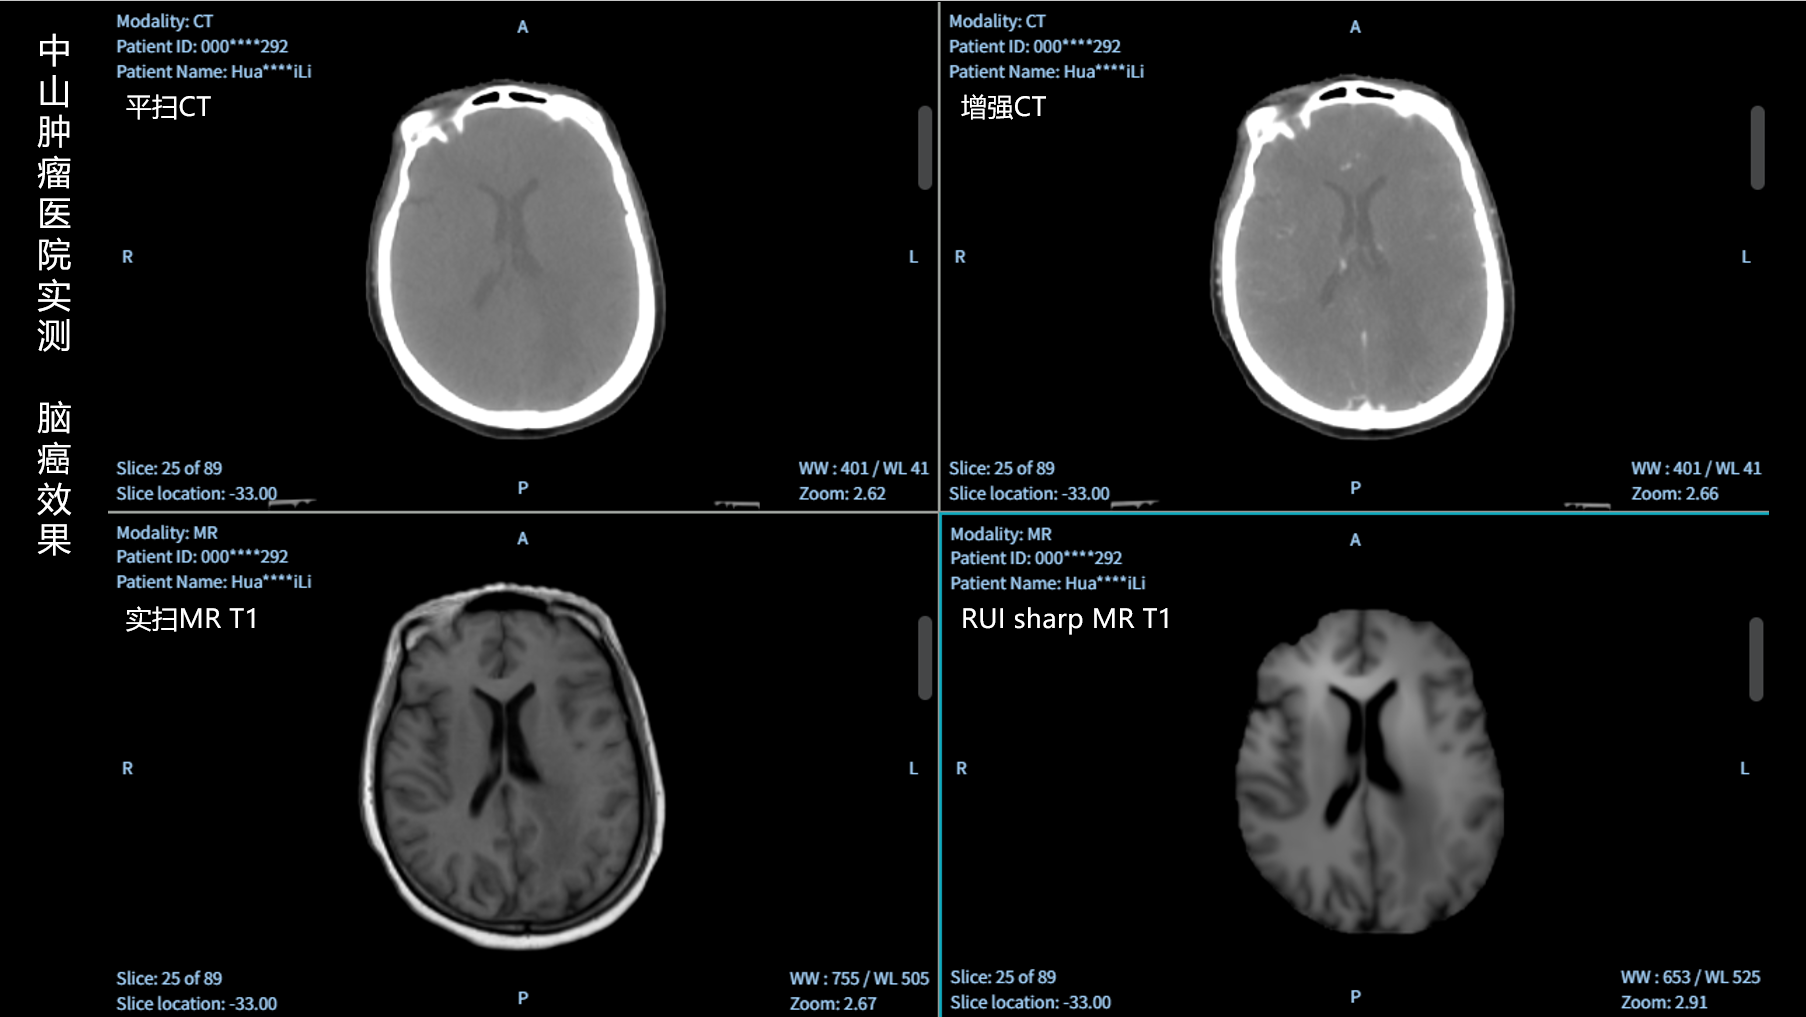

RUI sharp H(锐影)可在不依赖MRI的前提下,显著提升头部CT图像的软组织分辨率,为临床提供更高质量的辅助信息,尤其适用于MRI资源受限或较难配准的头颈部放疗感兴趣区勾画场景。

可大幅提高头部CT影像软组织分辨率,使肿瘤和周边器官显示更清晰,为放疗靶区勾画提供参考。

无需图像配准,CT和锐影图像同源,可匹配、叠加、"淡入淡出"显示。

实测效果